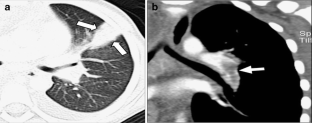

Fig. 1

Wedge-shaped peripheral consolidation was seen in eight children (36%) with PE and in two children (9%) without PE [odds ratio = 5.7, 95% confidence interval (CI): 1.2 to 30, p = 0.03]. There were no significant differences in the frequency of other findings between the groups (all p-values > 0.10). Prior history of neoplasm was the only independent risk factor significantly associated with the presence of PE (p = 0.006).

Wedge-shaped peripheral consolidation is significantly associated with PE on CTPA studies of children. The identification of a wedge-shaped peripheral consolidation in children should alert radiologists to carefully evaluate for concurrent PE.